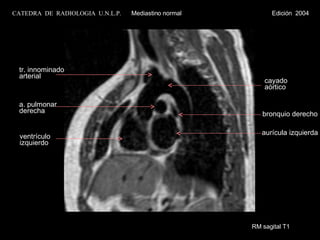

RM sagital T1ventrículo izquierdo aurícula izquierda cayado aórtico a. pulmonar derecha bronquio derecho tr. innominado arterial CATEDRA DE RADIOLOGIA U.N.L.P. Mediastino normal Edición 2004